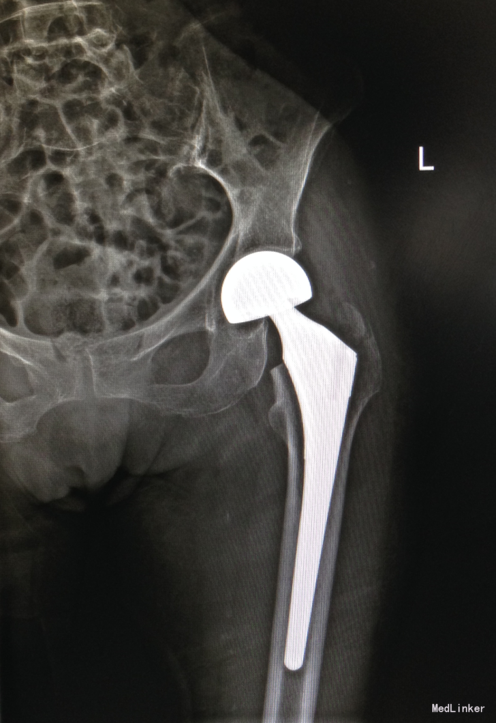

诊断:左侧股骨颈骨折 治疗:左侧人工股骨头置换

随访:术后2周手术切口愈合好。患者6周逐渐生活自理。6个月后功能康复致术前水平 讨论:术后应告诉患者接受正规的抗骨质疏松治疗。